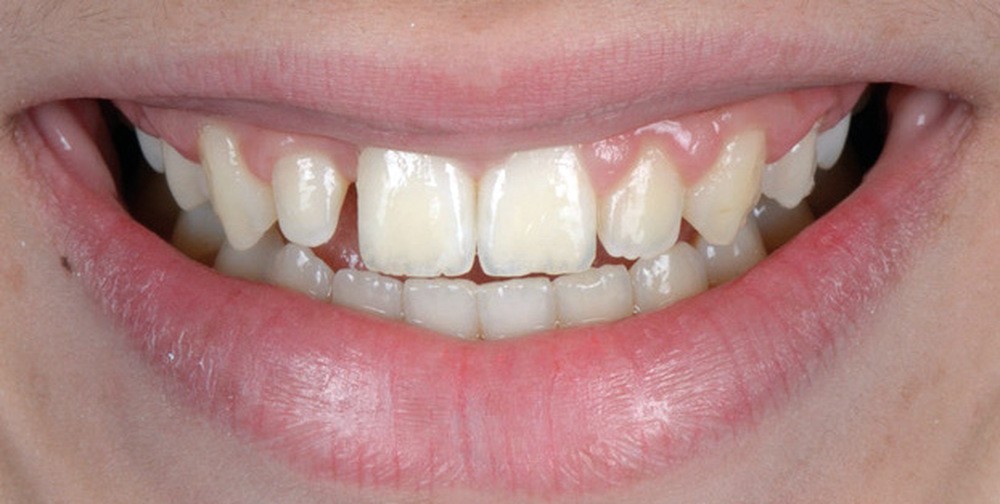

Le Pr Olivier Sorel insistera sur l’importance du respect des formes et des proportions anatomiques, pour éviter de voir apparaître, notamment chez les adultes, de très inesthétiques triangles noirs lors de la phase d’alignement (fig. 6a-b). Il présentera sa démarche diagnostique (évaluation de la forme des dents et de la dysharmonie dento-dentaire, fig. 7a-c) et l’intégration de la réduction amélaire proximale au plan de traitement, afin de s’assurer, en fin de traitement, la présence de papilles gingivales et donc d’un sourire harmonieux (fig. 8a-d).